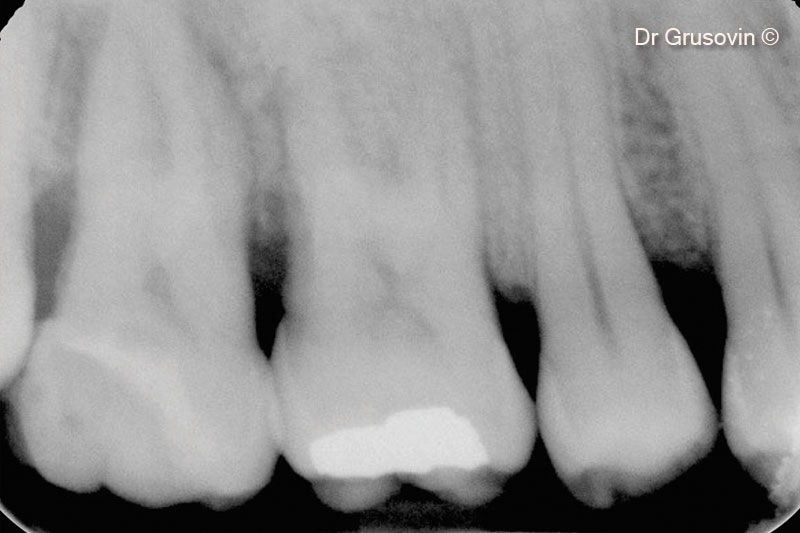

3. X-ray #16